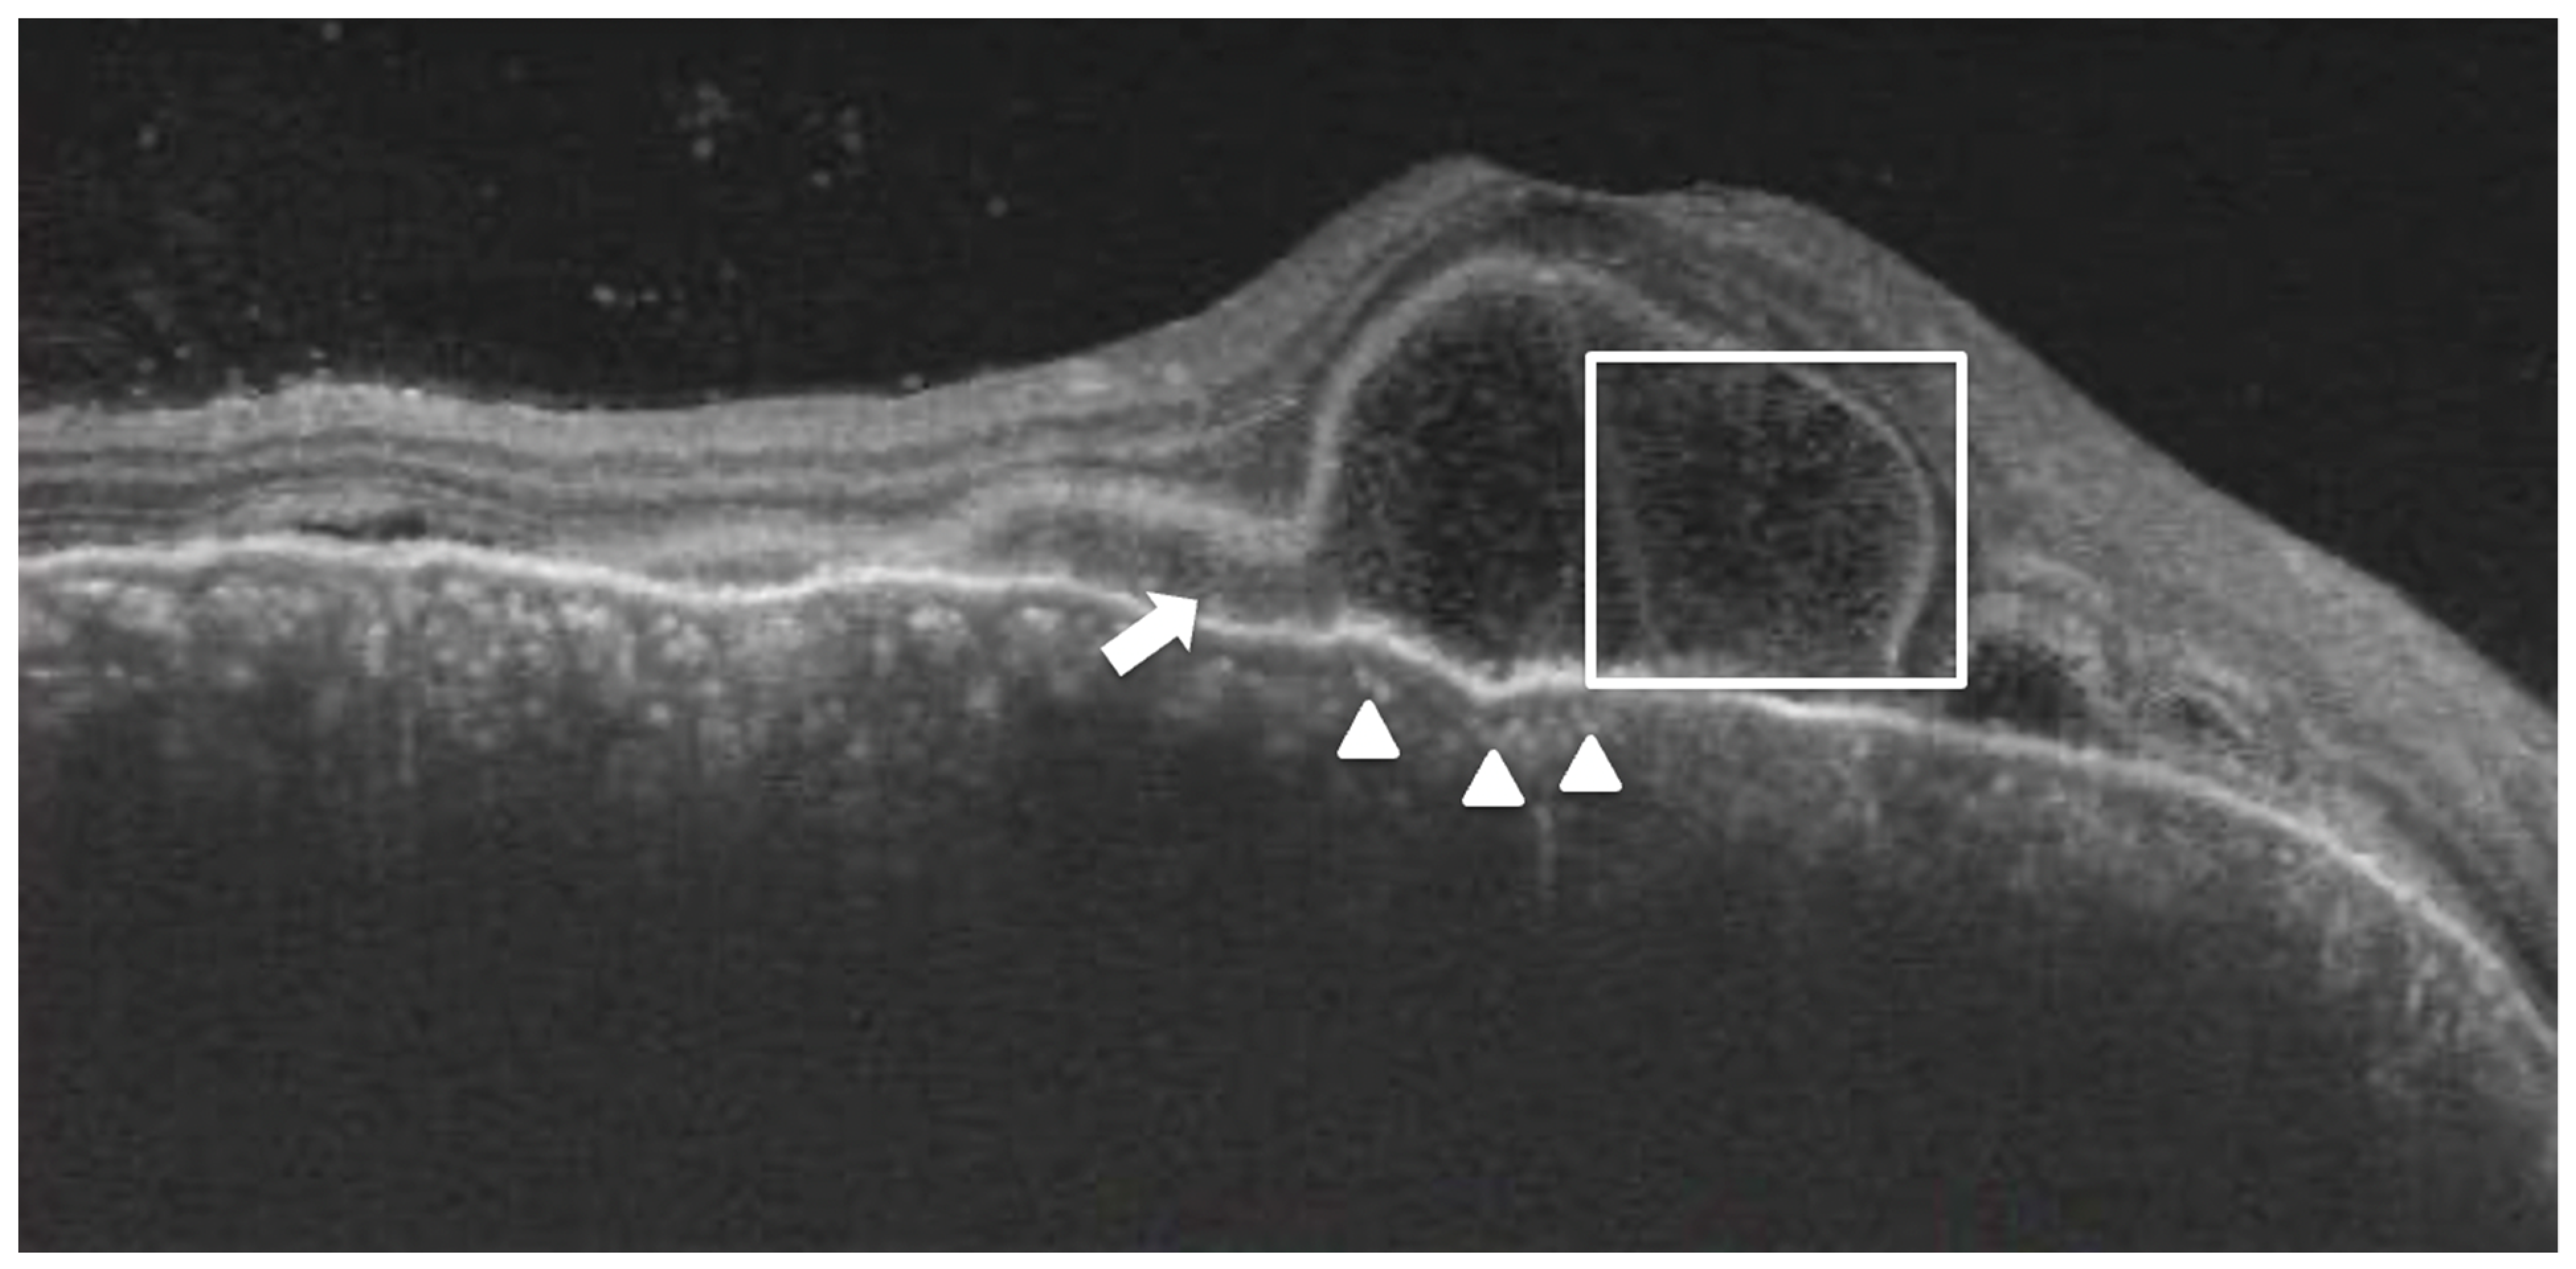

Figure 4. A 32-year-old lady with a diagnosis of acute Vogt-Koyanagi-Harada disease. The right eye shows bacillary layer detachment (white box) with subretinal hyperreflective material (white arrow) and choroidal hyperreflective dots (white arrowhead).

Subretinal hyperreflective dots were defined as hyperreflective dots below the neurosensory retina and over the RPE without associated back shadowing (Figure 3B). Choroidal hyperreflective dots were defined as circumscribed dots within the choroid seen on an OCT scan having equal or higher reflectivity than the RPE band (Figure 4). Bacillary layer detachment was defined as a split of the neurosensory retina at the level of the myoid zone in the photoreceptor layer (Figure 4). RPE vacuolations were defined as hypo reflective cavities within the RPE (Figure 3A).